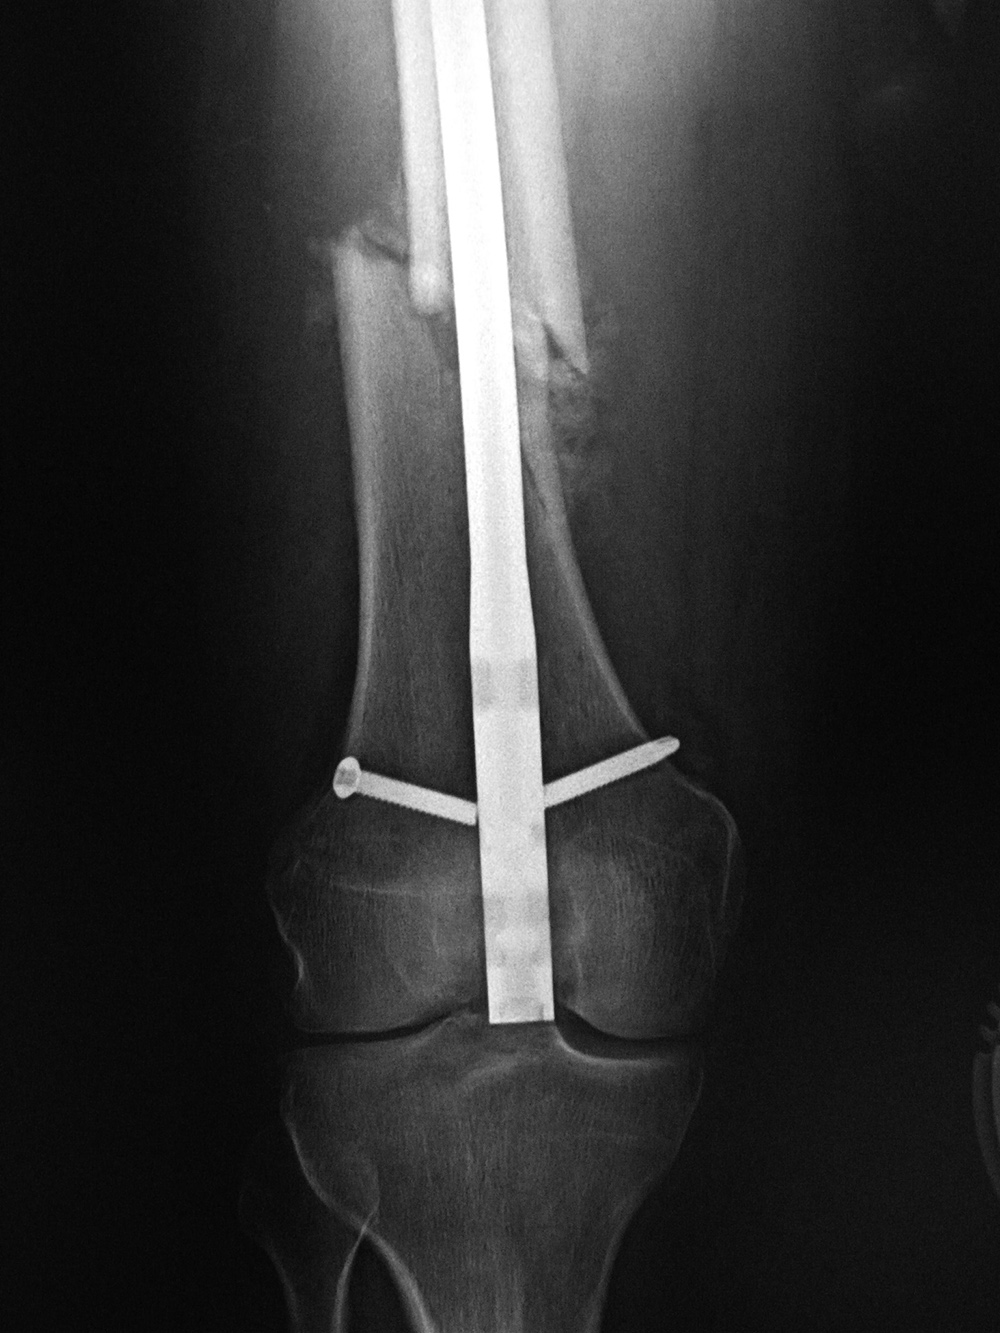

| Male patient with proximal tibia and fibula fractures treated by intramedullary nail and supplemental one-third tubular plate. Initial intraoperative fluoroscopic AP and lateral images (left two images) show the plate (arrow on lateral image). The patient ambulated against advice and was lost to follow-up. Two months later he again presented (right two images) to the clinic. There is now tibia fracture migration, and the proximal medial to lateral interlocking screw has backed out (AP view). The lateral view demonstrates fracture displacement with flexion deformity. The nail has troughed outside the proximal anterior tibia and is sitting within the soft tissues. The supplementary plate is broken, there is a broken interlocking screw, and abundant fracture callus is present. |